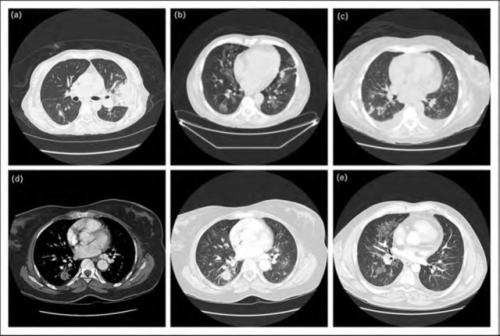

pulmonarymucormycosis

图片尺寸1596x1196

图片尺寸500x336